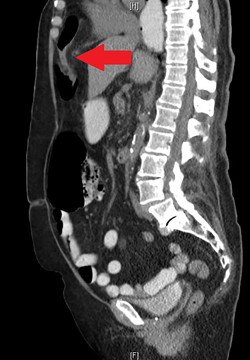

During the hospitalization, initial cardiac workup with 12-lead electrocardiogram and serial troponins was negative. The patient’s oncologic medications were held without improvement of the pain as well as to prevent leukopenia and neutropenia, if surgery was indicated. Palliative care was unable to achieve adequate pain control with oral and IV medications, and the patient did not want to pursue hospice care. Surgical consultation was obtained, and further evaluation with a CT scan of the chest, abdomen and pelvis with oral and IV contrast demonstrated an anteromedial diaphragmatic defect through which a prominent amount of mesenteric fat and a portion of the colon herniated representing a Morgagni hernia (Figs. 1–4). An increase in the size of the previously known PEH as well as the Morgagni hernia was noted. Due to continued chest pain unrelieved by opioids, a joint decision was made between surgeon, oncologist and the patient to proceed with surgery. She underwent successful robotic laparoscopic repair of the Morgagni hernia and PEH with dulex mesh for reinforcement. Her chest pain subsequently resolved. The patient gradually tolerated oral feeds and was eventually discharged in stable condition.

A CT chest, abdomen and pelvis with PO and IV contrast in 2017 shows bowel gas with mesentery herniating anteriorly through a diaphragmatic defect, consistent with a Morgagni hernia (red arrow) that has increased in size since 2015.